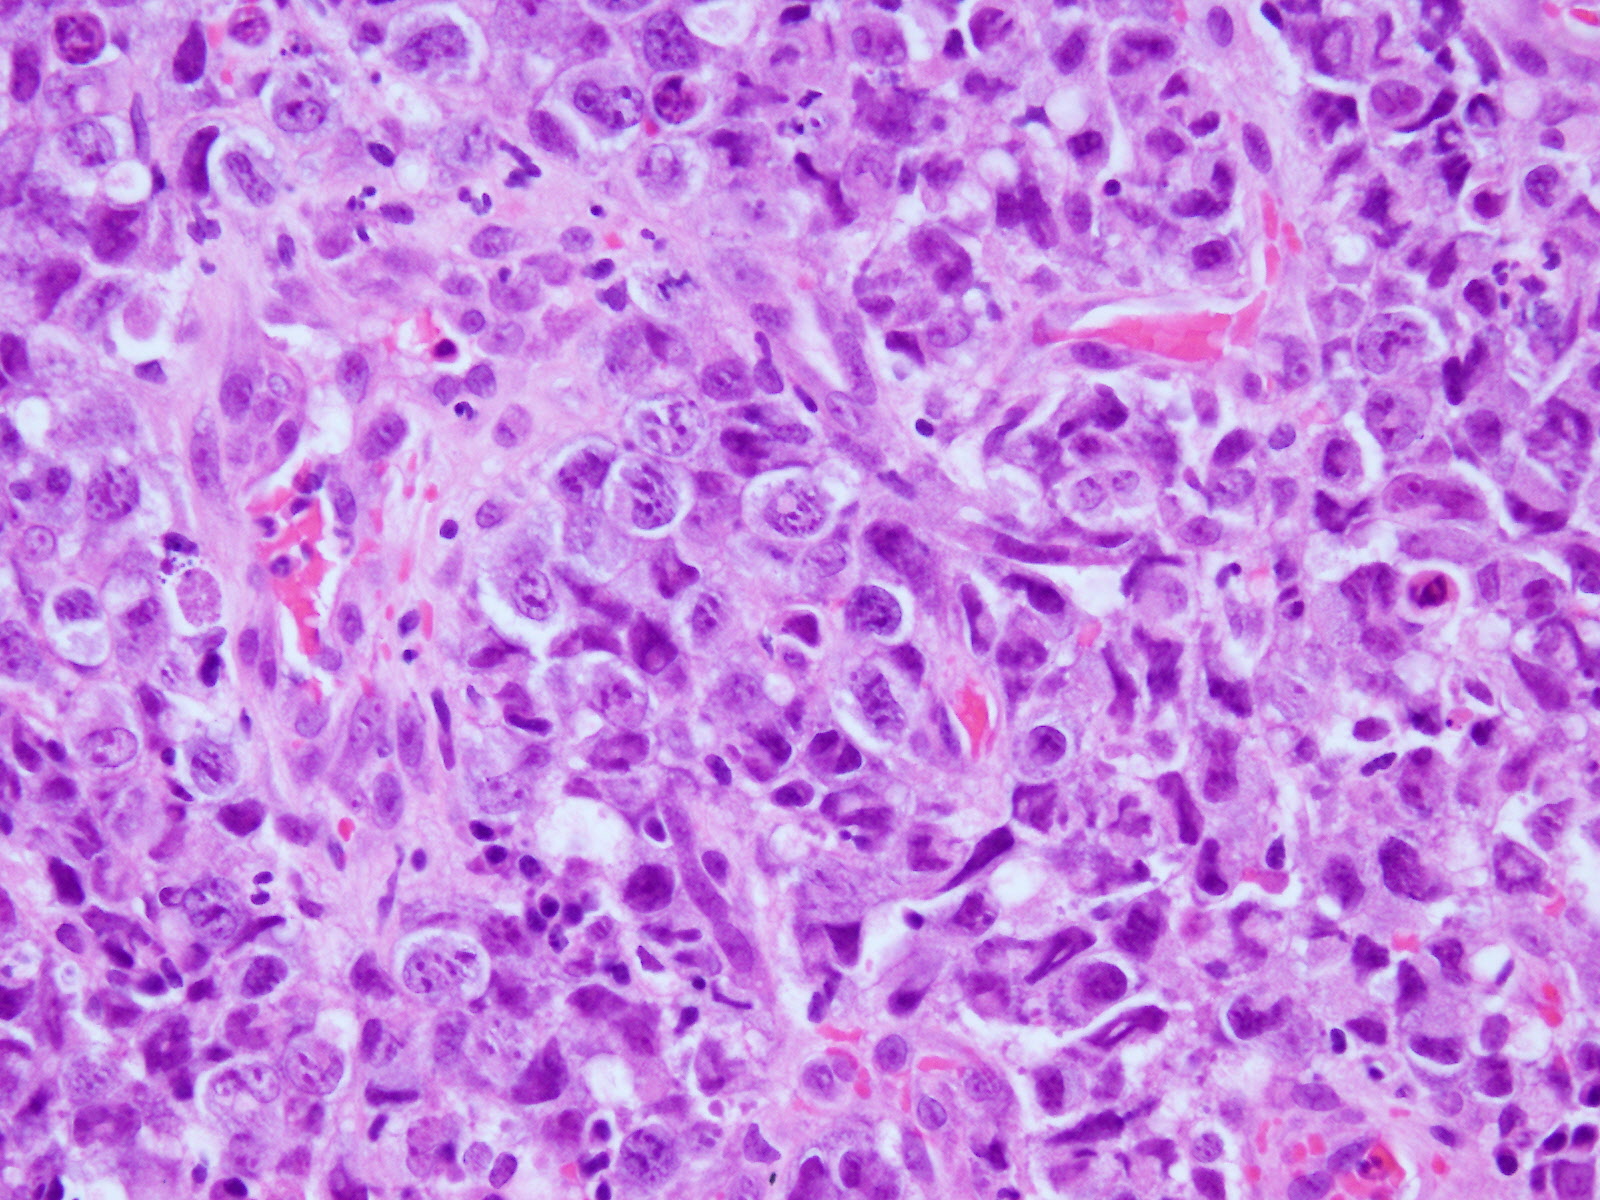

炎症性背景に、NC比増大、核形不整、核小体肥大を示す大型の細胞が弧在性に多数認められた。異型細胞は核異型が強く、一部、結合性を示すような細胞もみられた。

未分化大細胞型リンパ腫は大型の細胞がみられ、核異型が強く、結合性を示すものもある。そのため、ホジキンリンパ腫や癌との鑑別を要する。

細胞質内空砲が多数みられ、ギムザで好塩基性を示すことからリンパ腫が示唆される。

馬蹄形核、ドーナツ状核は未分化大細胞型リンパ腫の特徴的な細胞像であり、特徴を知っていれば診断可能な症例でもあるため今回症例提示した。